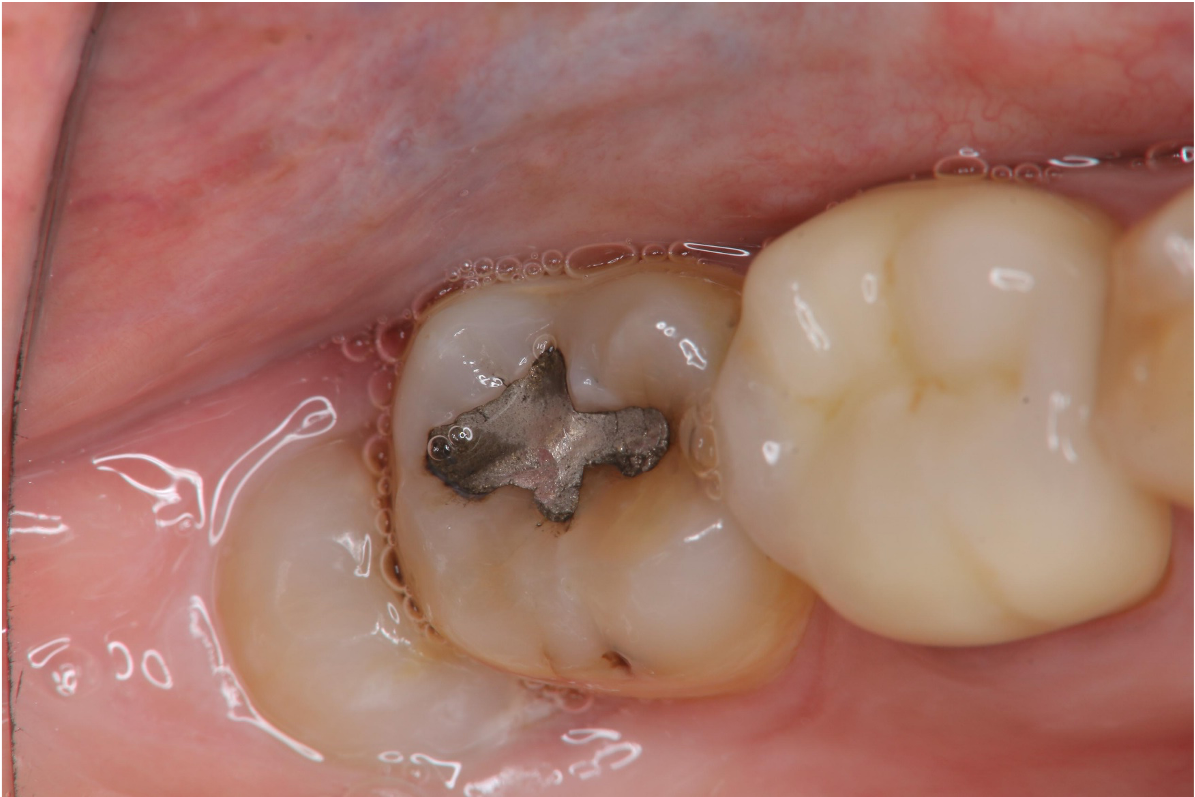

治療前,右下阻生齒深度蛀牙

治療前,環口X光,深度蛀牙